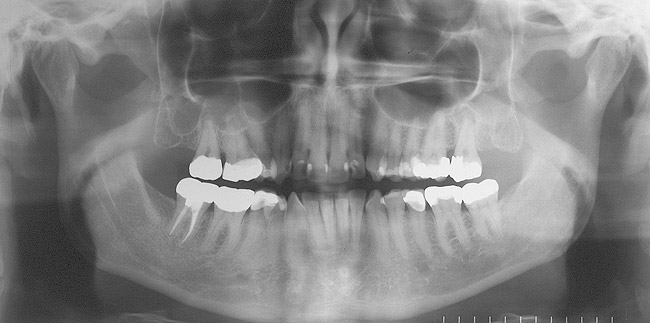

PARODONTAL: Evaluarea parodontală a evidenţiat adâncimi de sondare de 2-3mm în sextantele frontale şi de 2-5mm în cele posterioare. În regiunile laterale s-a observat o uşoară sângerare generalizată la sondare. Examinarea radiologică a obiectivat o pierdere osoasă orizontală generalizată uşoară spre moderată de 1-3mm. S-a descoperit un defect osos vertical pe faţa mezială a molarului 1.7. cu o adâncime de sondare asociată de 5mm (fig. 3). S-a stabilit un diagnostic parodontal de AAP tip II (parodontită uşoară).

Risc: redus

Prognostic: global bun, cu prognostic acceptabil specific molarului 1.7., datorită defectului său osos vertical mezial.

BIOMECANIC: Examinarea radiologică a identificat patologie apicală la nivelul molarilor 2.7. şi 1.7. (fig. 3, 4). Era vizibilă o leziune radiologică difuză, mixtă (fig. 4) apical de 1.6. şi 1.5., având un aspect care sugera un chist mucos de retenţie.1 Clinic, dinţii 2.7. şi 1.7. s-au dovedit a fi devitali la testare, în timp ce 1.5. şi 1.6. erau vitali.

S-au constatat carii dentare active la nivelul 1.7., 4.6. şi 4.4. Dinţii 1.7., 1.6., 2.4.-2.7., 4.4., 4.7. prezentau restaurări cu adaptare defectuoasă. Dinţii 1.7.-1.5., 2.5.-2.7., 3.5.-3.7., 4.5.-4.7. au fost notaţi cu structură compromisă datorită dimensiunii, tipului şi profunzimii restaurărilor. În plus, segmentul dentar 3.2.-4.2. prezenta semne precoce de eroziune chimică la nivelul muchiilor incizale. Corespunzător 1.6. s-a obiectivat o exostoză osoasă pe versantul vestibular (fig. 5), generând o înălţime scurtă a coroanei clinice şi un compromis restaurator ulterior.

Risc: crescut

Prognostic: slab; irecuperabil pentru dinţii cu carie dentară netratată.